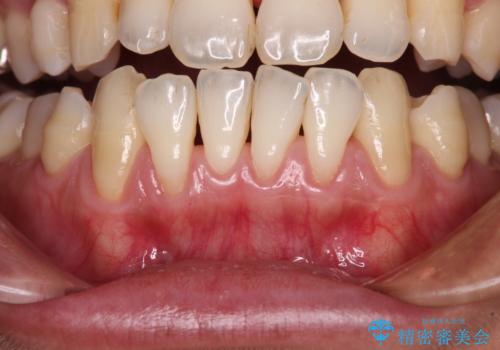

年々下がる歯茎を何とかしたい 歯肉移植術による根面被覆

担当医 藤巻太一朗